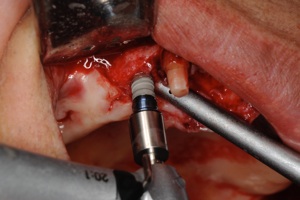

1.インプラントの手術 1,2時間程度で終わります。麻酔は局所麻酔です。

1次オペ

インプラント

埋入

当日

縫合